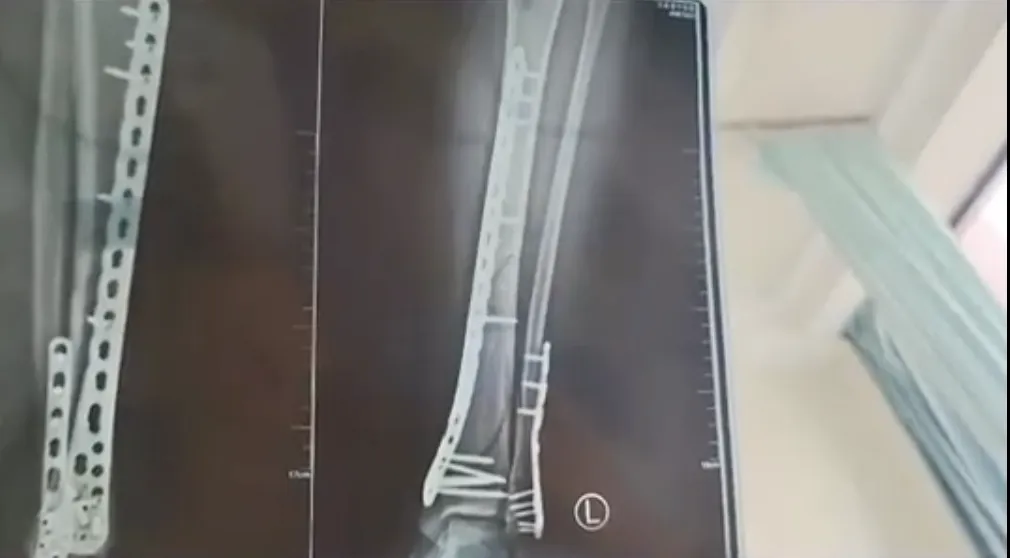

今年6月,甘肃一女子穿7厘米厚底洞洞鞋下楼,崴脚致粉碎性骨折。消息一出,不少网友都表示“怕怕”。